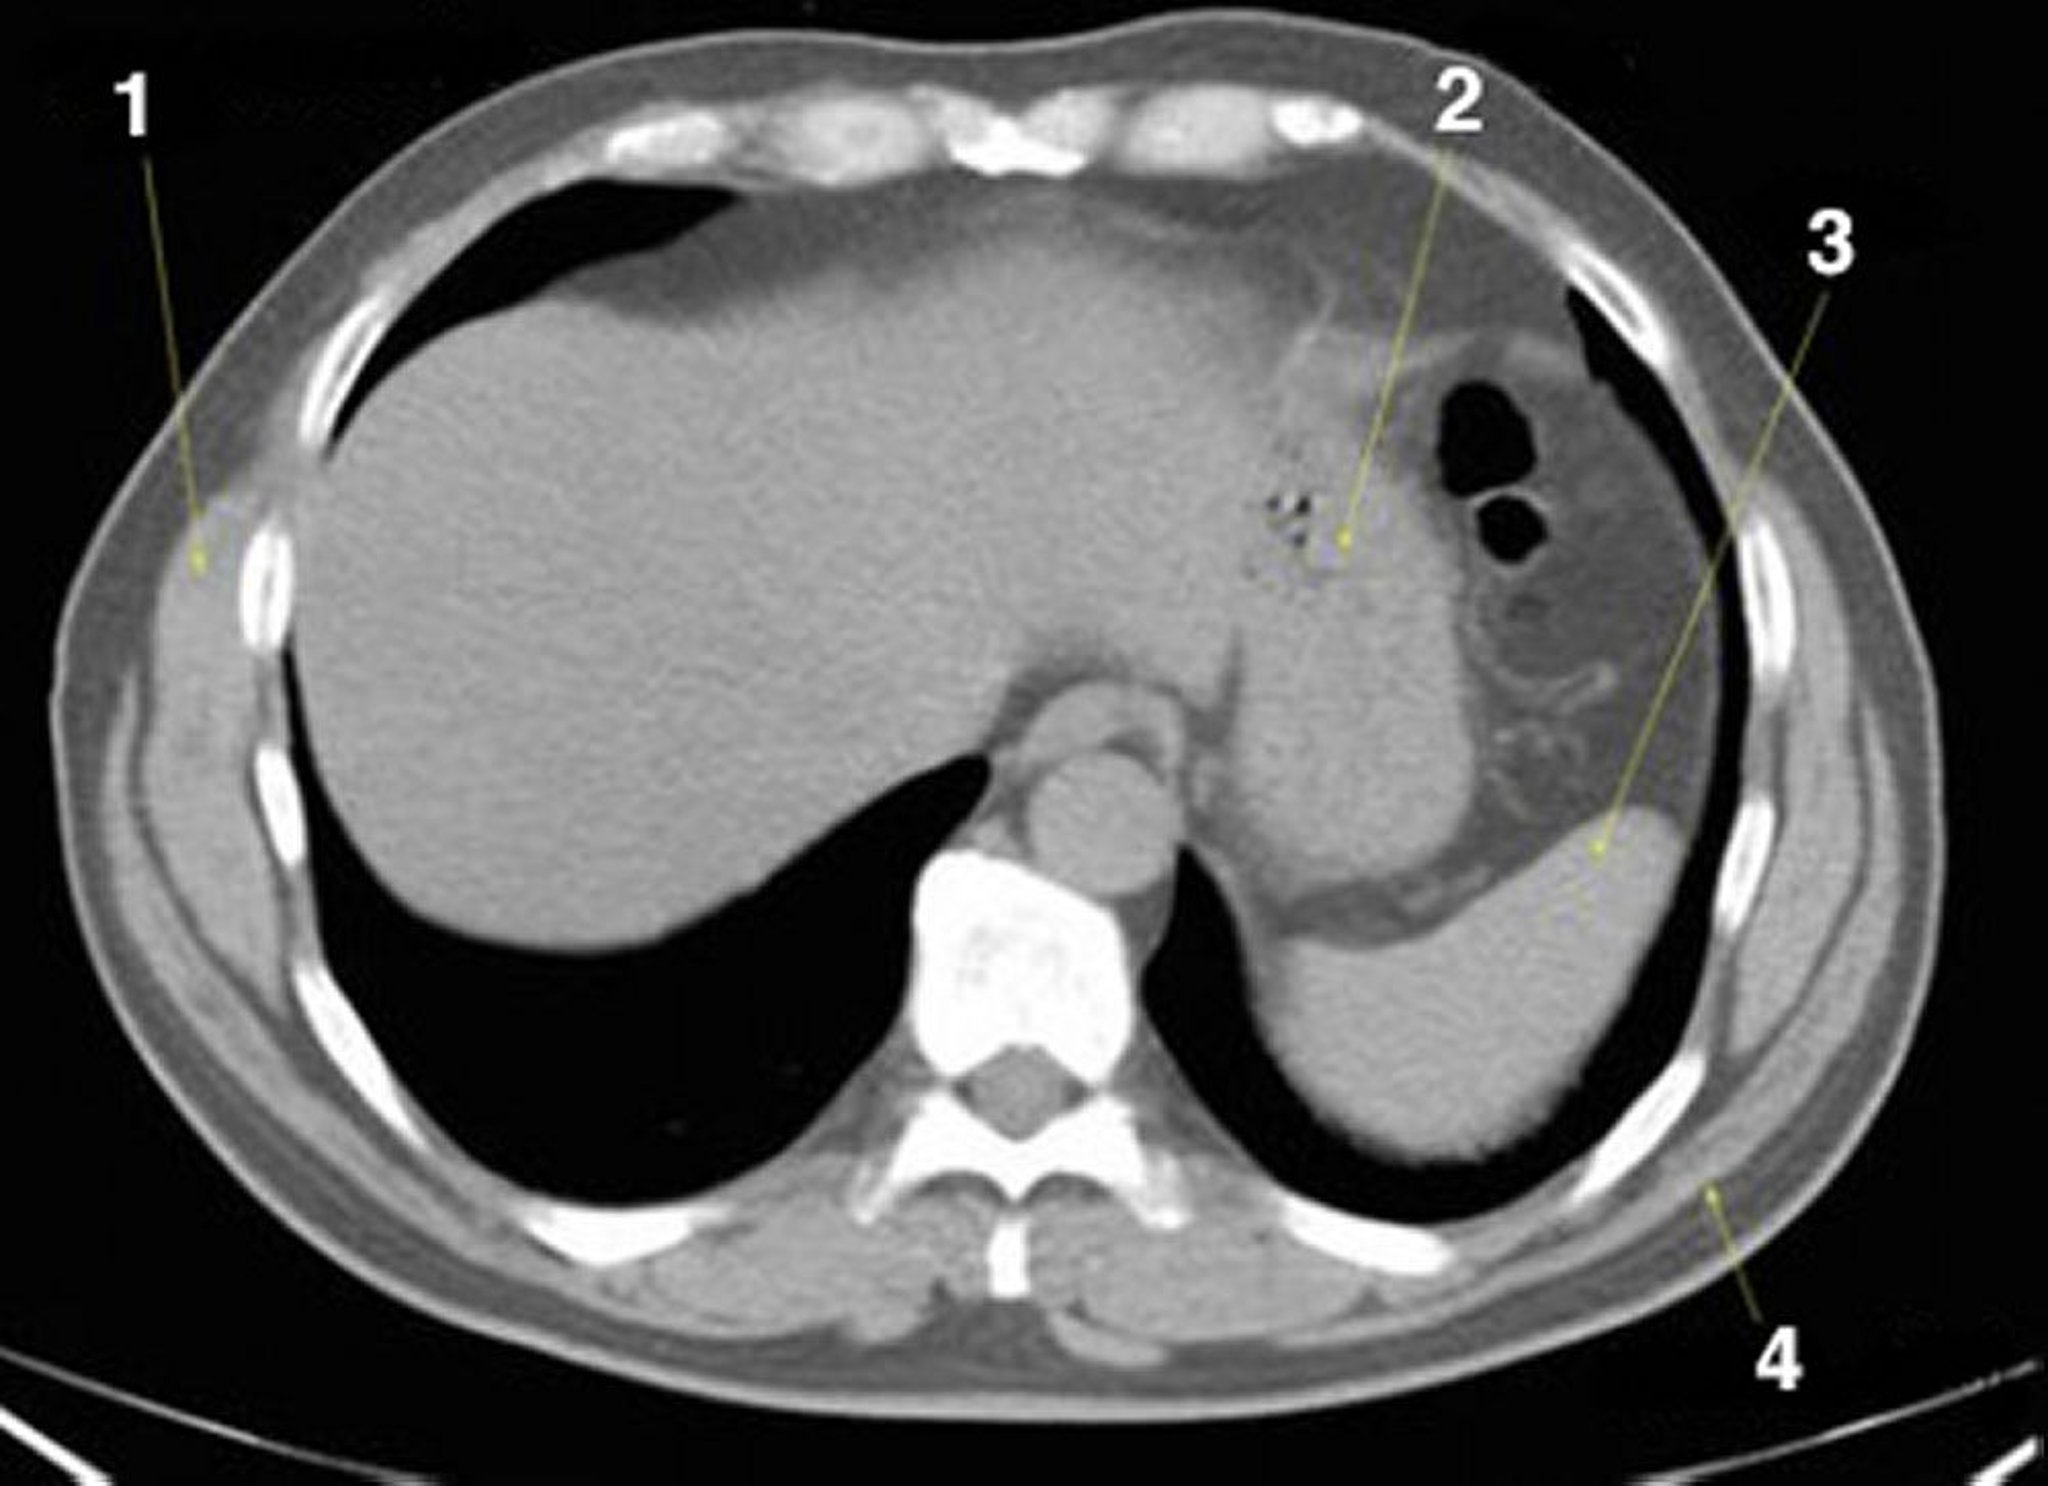

TC senza contrasto dell'addome e della pelvi che mostra un'anatomia normale (Slide 2)

1 = serratus anterior; 2 = stomaco; 3 = milza; 4 = latissimus dorsi.